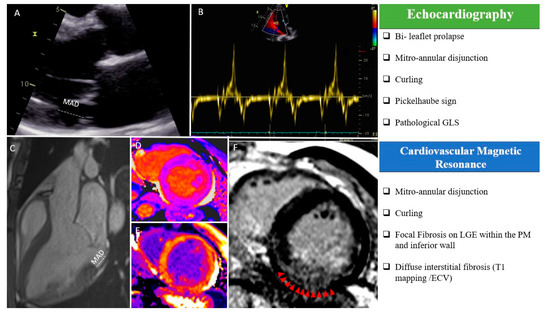

Figure 1.

“Red Flags” in echocardiography and cardiac magnetic resonance imaging (CMR): (A) MAD measured in a parasternal long-axis view (transthoracic echocardiography); (B) “Pickelhaube sign” during transthoracic echocardiography; (C) MAD measured in a steady-state free precession three-chamber view during CMR; T1 mapping native (D) and after gadolinium injection (E); macroscopic fibrosis in the inferior basal wall highlighted with red arrows in a free-breathing LGE sequence (F). ECV, extracellular volume; LGE, late gadolinium enhancement; MAD, mitro-annular disjunction; PM, papillary muscle, GLS: Global Longitudinal Strain.

TTE and transesophageal echocardiography (TEE) are the reference techniques to evaluate leaflet anatomy [12]. The “classical” definition of MVP is a single or bileaflet prolapse of at least 2 mm beyond the long-axis mitral annular plane, with or without leaflet thickening. MVP should only be diagnosed from a strict long-axis view (i.e., a parasternal or apical long-axis view), as these views cut the saddle-shaped mitral annulus at its highest point: Looking for MVP from other echocardiographic views may result in the overdiagnosis if MVP due to the complex three-dimensional shape of the mitral annulus [13]. Limitations due to a poor acoustic window may be easily overcome by TEE, and the use of three-dimensional echocardiography additionally provides a detailed evaluation of the mitral valve anatomy in “surgical view,” of the mechanism of regurgitation (including the distinction between Barlow’s disease and fibroelastic deficiency), and of the surgical reparability of the valve. While the degree of mitral regurgitation itself has not been associated with VA or SCD [7,8,14], the combination of a myxomatous valve (Barlow’s disease) with bileaflet involvement and marked leaflet redundancy during echocardiography should already raise the suspicion of aMVP and justify dedicated investigation to look for additional high-risk features associated with the MVP syndrome [7]. The tugging of the posteromedial PM in mid-systole by the myxomatous prolapsing leaflets causes the adjacent postero-basal left ventricular wall to be pulled sharply toward the apex. This brisk mid-systolic apical motion can be captured with tissue Doppler imaging of the postero-basal segment in the long-axis apical view, showing a spiked configuration of the Doppler spectrum in mid-systole, the so-called “Pickelhaube” sign (Figure 1B) [15]. It reflects the abrupt stretching of the myocardium and papillary muscles by the prolapsing valve, which may serve as a mechanical trigger of Premature Ventricular Contraction (PVC) or ventricular arrhythmia. Recent data have suggested that a spiked tissue Doppler systolic velocity ≥16 cm/s is a risk marker and should be included in the routine echocardiographic evaluation of MVP patients [15]. Regional systolic myocardial motion can also be captured by speckle-tracking echocardiography, and in a cohort of MVP patients with significant mitral regurgitation, lower global longitudinal strain values and prolonged mechanical dispersion are independently associated with the occurrence of symptomatic VA [16,17]. Pathological deformation patterns with increased pre-stretch and post-systolic contraction have also been described in the basal segments of MVP patients [18], and patients with Barlow’s disease show enhanced strain in the basal segments compared to patients with fibro-elastic deficiency or normal controls [19]. The potential importance of these features for arrhythmic risk stratification will require further investigation.

First mentioned by Bharati et al. [20], MAD refers to a displacement of the insertion point of the posterior mitral valve leaflet, which accounts for a wide separation between the left atrial wall and the left ventricle. The diagnosis of MAD is usually made in systole by measuring the distance between the posterior leaflet insertion into the left atrial wall and the base of the LV free wall [21]. This should be performed in a parasternal long axis view in echocardiography or in three-chamber view during CMR [22].

The assessment of MAD is of importance, as it has emerged as an independent risk factor for VA in several studies, probably due to its link to the mechanical stretch of the myocardium [3]. While larger degrees of MAD correlate with higher incidence of complex VA, the cut-off for MAD diagnosis is not uniformly defined. Usually the histological reference of >5 mm at the posterior leaflet level, firstly described by Hutchins et al., is considered in most echocardiographic studies (Figure 1A) [23]. However, it must be kept in mind that the circumferential extension of MAD is variable, and sometimes, the identification of MAD using TTE may be challenging [24]. The better acoustic window on TEE may overcome the disadvantage of insufficient TTE image quality, but comes at the cost of a more invasive examination [12]. On the contrary, the extent of longitudinal MAD distance located in the posterolateral wall is easily assessed by CMR [22] (Figure 1C). Essayagh et al. [8] compared TTE and CMR for the detection of MAD and found a low sensitivity (65%) but a high specificity (96%) for TTE. A recent study compared TTE, TEE, and CMR and showed only a moderate agreement between TTE and CMR, while a good agreement was found between TEE and CMR [25]. Even if not recommended in routine evaluation, cardiac computed tomography also allows to measure the length of MAD [26].

Notably, an unusual systolic motion of the posterior mitral ring and the adjacent myocardium may also be found in patients with aMVP (“Curling”) [3,10]. This specific movement has been linked in several series with the presence of MAD and it contributes to the paradoxical increase in the mitral annulus diameter during systole and the relative hypertrophy of the hypermobile postero-basal segments [7]. It may be associated with the development of LV fibrosis, accounting for the excessive mobility of the MV apparatus and systolic stretch of the myocardium closely linked to the valve. For the moment, only a visual non-quantitative assessment is typically performed, while no specific cut-off has been identified (Video S1: Curling motion during transthoracic echocardiography; Video S2: Curling motion during CMR; Supplementary Materials).

The presence of fibrosis at the PM and inferior LV wall level is another key feature of aMVP and has been proposed as an independent risk factor for VA and SCD [27]. CMR is the only imaging technique that allows for a detailed evaluation of myocardial tissue characteristics, but until now, it has not been routinely used in patients with MVP.

Basso et al. [27] demonstrated in 2015, by histopathologic analyses in young SCD victims with MVP and trivial mitral regurgitation, a high prevalence of myocardial fibrosis in the LV infero-basal wall and in the PMs. These findings were confirmed in vivo in a subpopulation of MVP patients with complex ventricular arrhythmias, in whom CMR showed a late gadolinium enhancement (LGE) distribution similar to the histopathologic findings observed in SCD victims. These myocardial fibrotic alterations have been confirmed in other studies [6,7,8,14,28], and are probably linked to the mechanical stretch acting upon the valve and the neighboring LV myocardium and could represent the arrhythmic substrate in patients with MVP. However, identification of LGE at the PM level and neighboring LV walls may be challenging even for CMR experts, and additional non-standard views may be needed to best visualize fibrotic regions in the myocardium (Figure 1F). Undoubtedly, this evidence supports the need for a CMR examination with LGE acquisitions in all patients with suspected aMVP.

Pradella et al. [33] and Bui H et al. [34] found globally higher native and lower post-contrast T1 myocardial values, suggesting the presence of interstitial fibrosis, but no association with complex VA was found (Figure 1D,F). However, their studies suffered from various limitations, in particular, the lack of a control group (patients with mitral insufficiency but without MVP) and the absence of a multivariate analysis considering the presence of other high-risk features. Moreover, Guglielmo et al. highlighted that patients with MVP have higher native T1 times compared to healthy controls, particularly in the basal and mid-LV inferolateral walls; higher T1 values were not correlated with MR severity, indicating that diffuse fibrosis may not only be a consequence of volume overload [35].